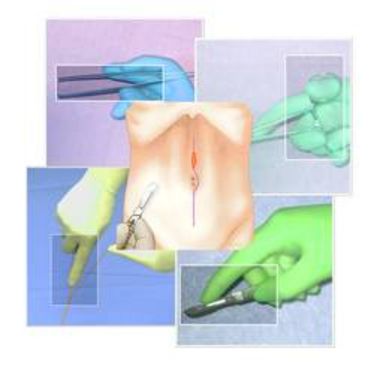

BASIC SURGICAL SKILLS

BASIC SURGICAL SKILLS

BASIC SURGICAL SKILLS

BASIC SURGICAL SKILLS

BASIC SURGICAL SKILLS

BASIC SURGICAL SKILLS